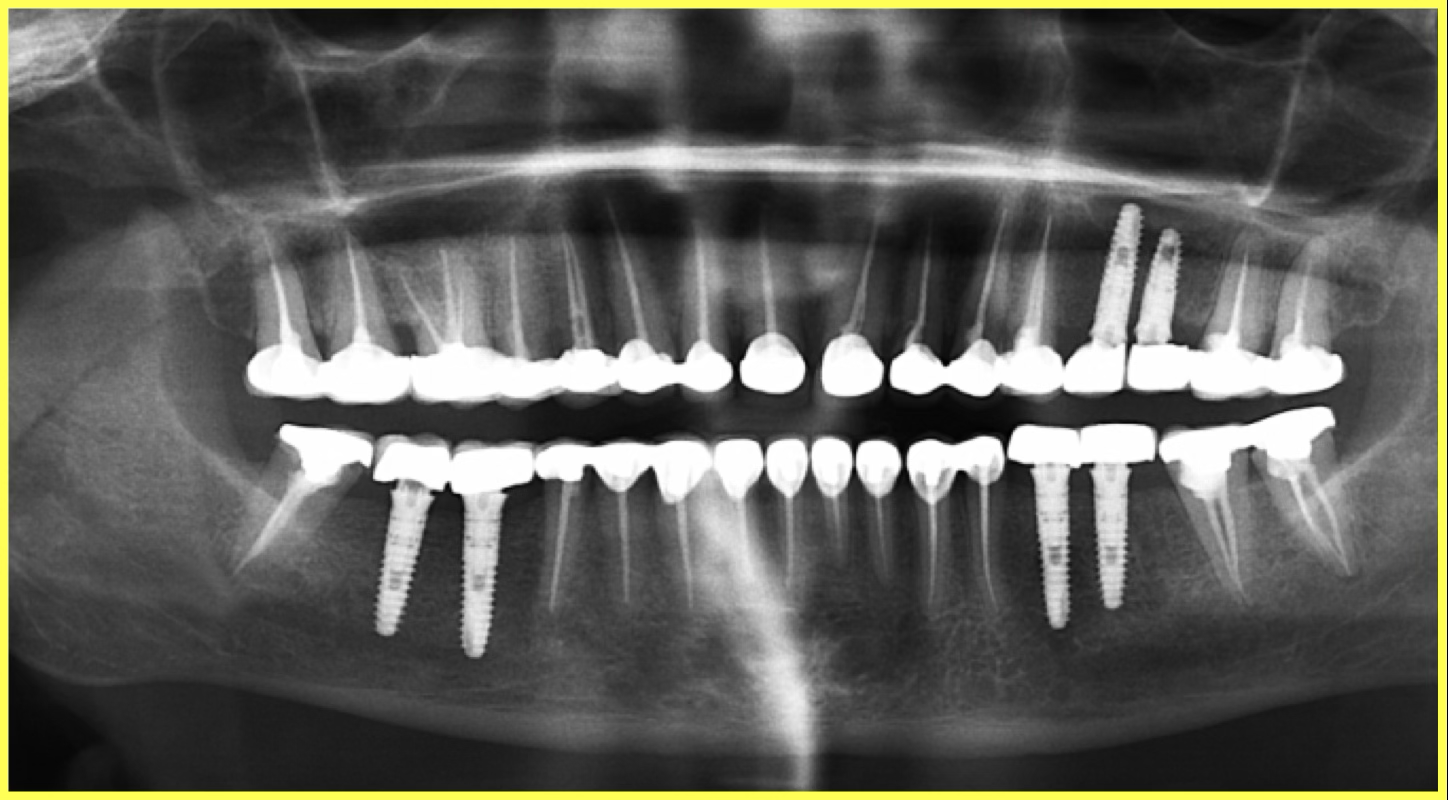

Strategic placement of 6 Dio dental implants in the regions of missing teeth using precise surgical protocols.

Permanent Porcelain Fused to Metal (PFM) crowns were custom-fabricated and cemented. Implants were delayed loaded after 3 months of healing.